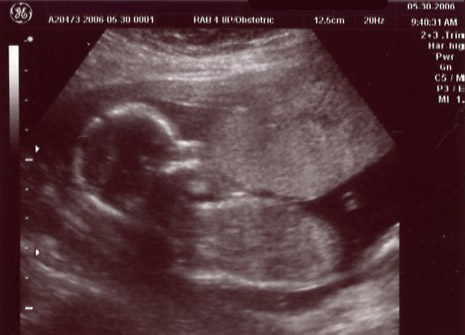

| May 30, 2006 - Sixteen Week Ultrasound! |

| Jen was feeling some pain this morning (May 30th), so to play it safe, she called her doctor. They said to come right in. We were obviously concerned, but they saw us right away and asked her a bunch of questions. They didn't think it was anything to be concerned with, but they

performed an ultrasound just in case. That too checked out and we left a bit relieved and happy to have even

more pics of our yet to be born angel. ~Chris |

Another profile shot |